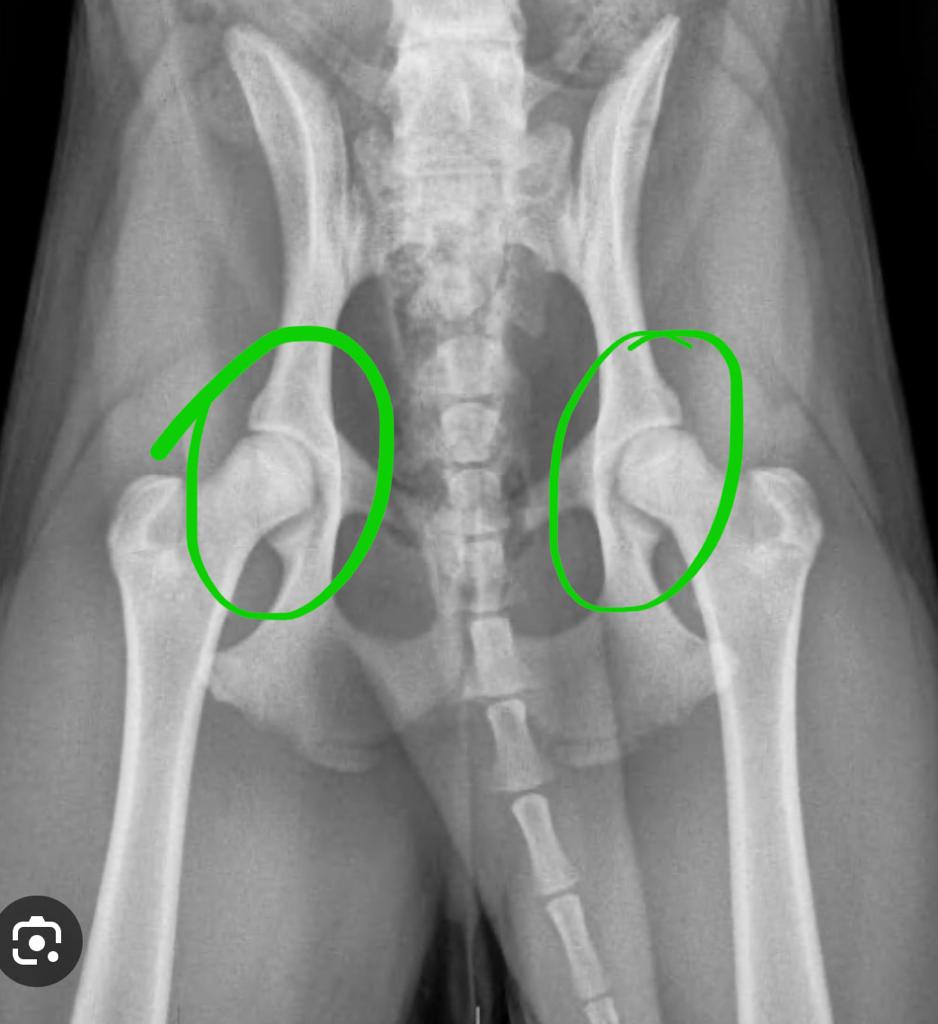

NORMAL DOG HIPS: